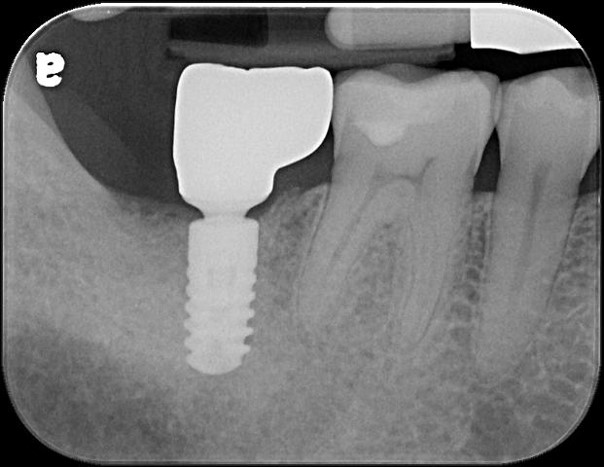

治療前,二次蛀牙,咬頭受損

蛀牙未到牙髓

當蛀牙破壞程度大